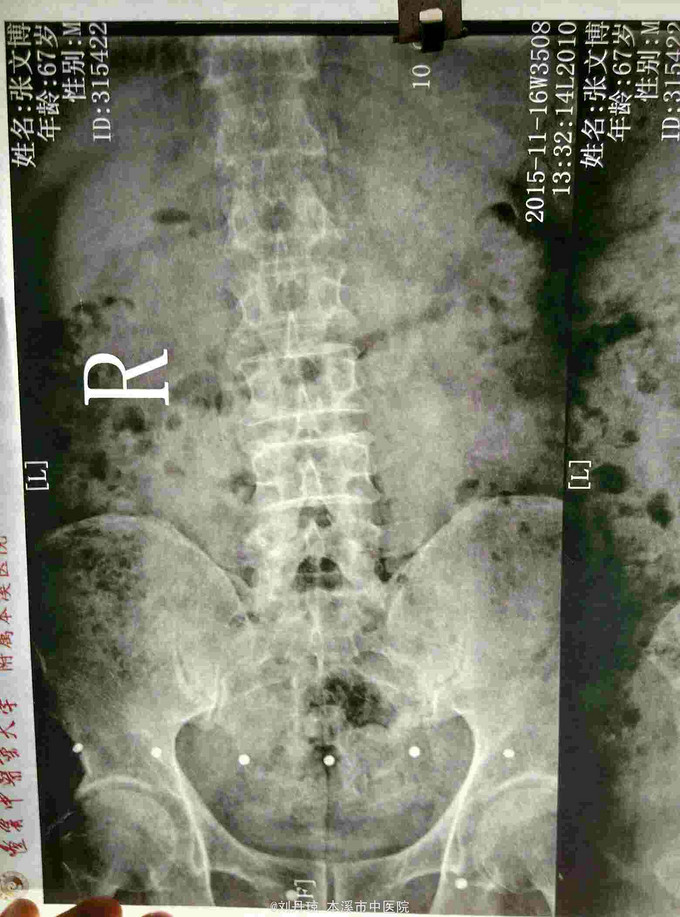

腰部间歇性钝痛伴左下肢放射痛麻木感半年。患者半年前无明显诱因感腰部间歇性钝痛伴左下肢放射痛麻木感,经多家医院治疗未见明显好转,今日来我院门诊求治,门诊医师以“ 腰椎间盘突出症、骶管囊肿 ”收入院治疗。

L4-S1棘突左侧1厘米压痛阳性,直腿抬高试验左40º右60º,加强试验左侧(阳性)右侧(阴性),腰椎功能障碍。左腿前外侧及足背外侧感觉减弱。 辅查CT: 腰椎间盘突出症、骶管囊肿